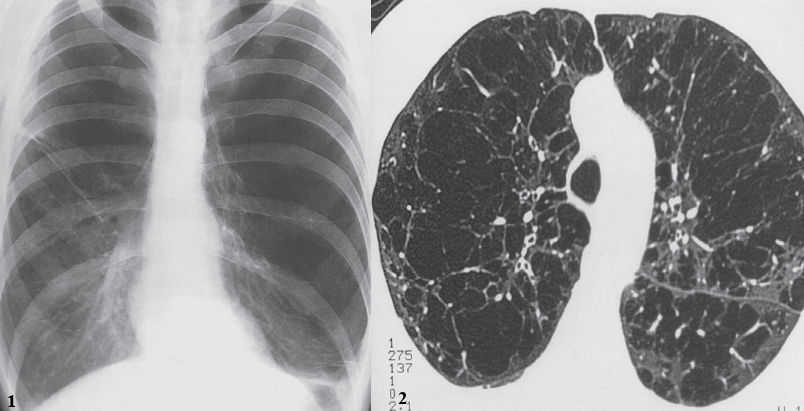

On x-ray chest PA view:

- Increased lung volume.

- The diaphragm is pushed down and becomes low and flat.

- The heart is elongated and narrowed.

- The ribs are widely spaced.

The diaphragm is low and flat and the ribs are widely spaced, indicating overinflation of the lungs. - The peripheral vessels in most of the left lung and the upper half of the right lung are small and attenuated, indicating lung destruction.

CT showing innumerable bullae.